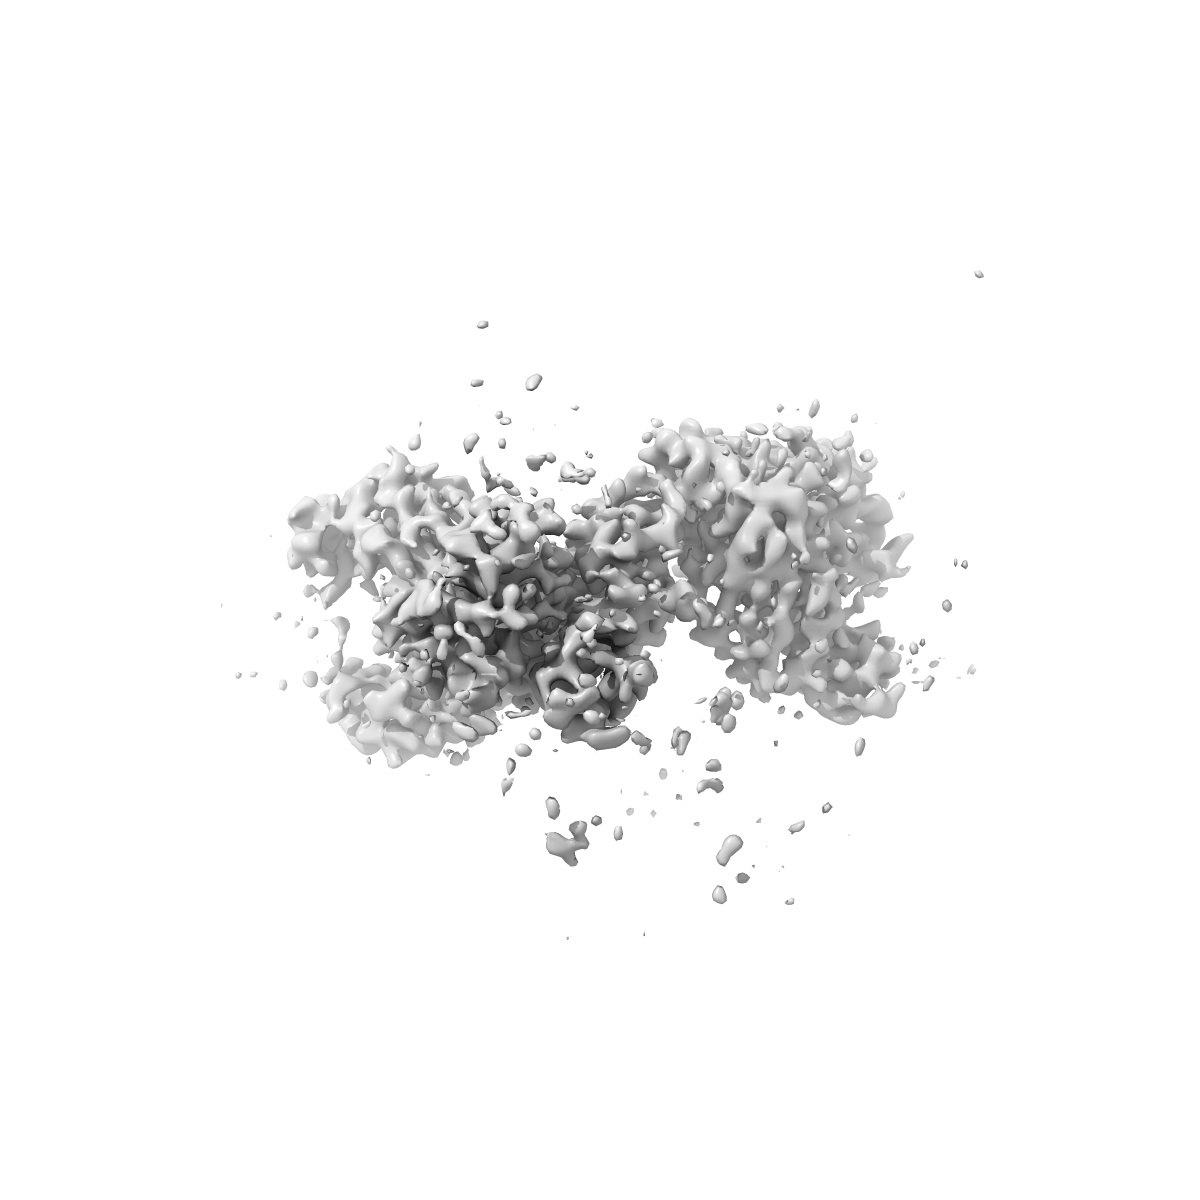

Cryo-EM structure of SARS-CoV-2 spike protein in complex with double nAbs 8H12 and 1C4 (local refinement)

Single-particle3.77 Å

Sample: Cryo-EM structure of SARS-CoV-2 spike protein in complex with 8H12

Two antibodies show broad, synergistic neutralization against SARS-CoV-2 variants by inducing conformational change within the RBD.